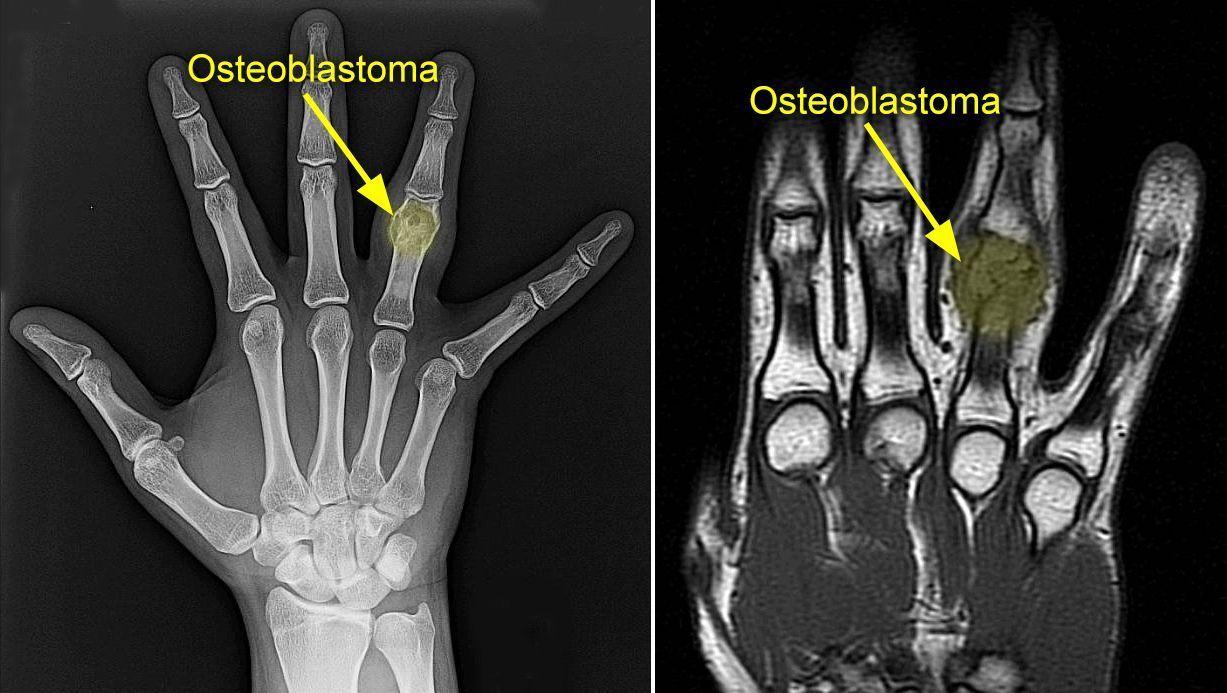

Estos tumores son muy poco frecuentes y suelen aparecer en la columna vertebral pero también en las piernas, las manos y los pies. Según los expertos, la localización más habitual de este tipo de lesiones "se encuentran comúnmente en la cara dorsal de las vértebras y huesos largos".

Para diagnosticar los osteoblastomas, los especialistas realizan radiografías y otras pruebas de diagnóstico por imagen como tomografía computarizada (TC) y resonancia magnética nuclear (RMN). "Para confirmar el diagnóstico de osteoblastoma, además, se toma una muestra de tejido y lo examina al microscopio (biopsia)", señalaron los expertos.